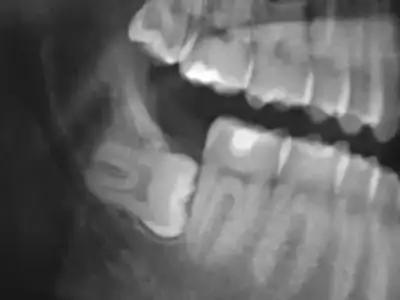

$gomulu_dis_agrisi.webp $GML-DI~2.webp

1.resimde dişin bir kısmı çıkmış

ikincisi ise nerdeyse tamamı gömülü bazende damak içinde kalıyor sen farketmiyorsun

farketmediğin bu diş ilerde diğer dişlerine baskı yapıyor ve çürüdüğü zaman sıkıntı yaratıyor bu gibi dişleri çekiyorlar zaten

varsa bir şüphen bence doktora git geç olmadan öğren röntgenini çekerler zaten